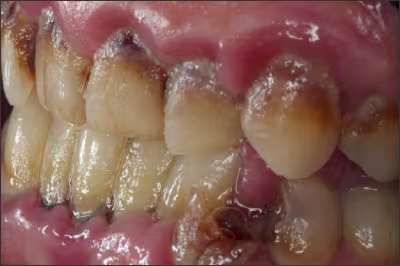

There is a higher incidence of dental caries seen in those using tobacco products as there is an increased acidity seen in the oral cavity and a decreased buffering capacity of the saliva.2

Periodontal Disease

To quote the 2014 Surgeon General’s report, “The evidence is sufficient to infer a causal relationship between smoking and periodontitis.”2 This was highlighted by Tomar and Asma, when they showed that 52.8% (8.1 million people) of periodontitis in the US population was attributable to current and former smokers.41 In addition, it was also demonstrated that quitting smoking reduced the risk of periodontitis.41